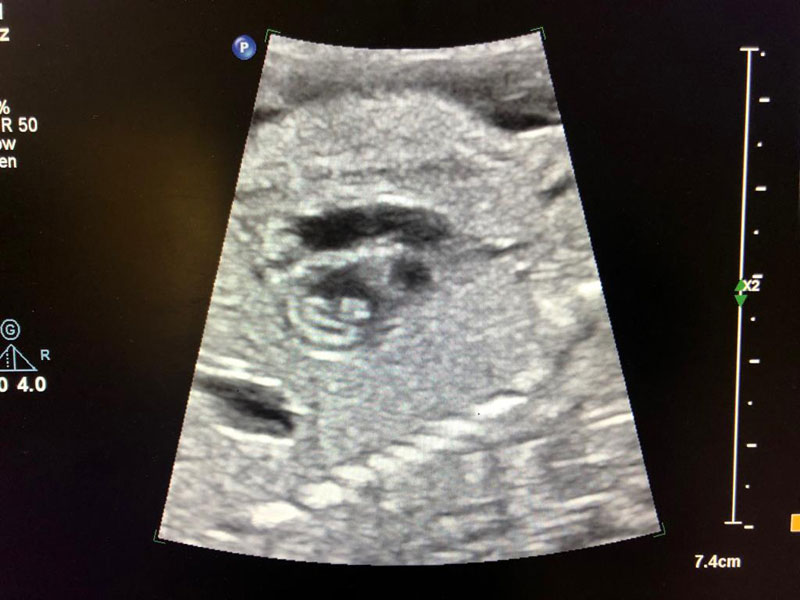

Cardiac activity of baby in mother’s womb can be seen at 22 days of gestation. By 12 weeks, heart of the baby is fully formed and functional in the mother’s womb. With the use of fetal echocardiography, we can see the structure and function of the baby’s heart. Any problem in the baby’s heart can be detected with 80-90% efficacy.

Ideal gestational age for performing this test is between 22-24 weeks of pregnancy but it can also be performed safely between 18-20 weeks Use of fetal echocardiography